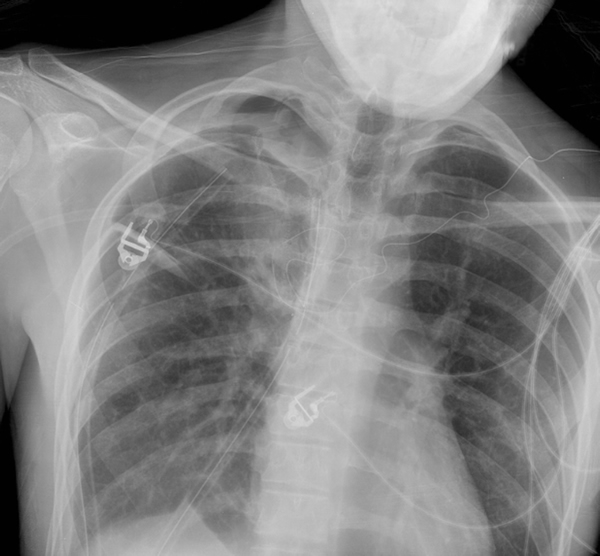

A pleurectomy is a surgical procedure in which part of the pleura is removed. View after a left sided decortication with partial removal of the visceral pleura shows the lung predominantly the lower lobe in the photo reinated. Surgical excision of a portion of the pleura.